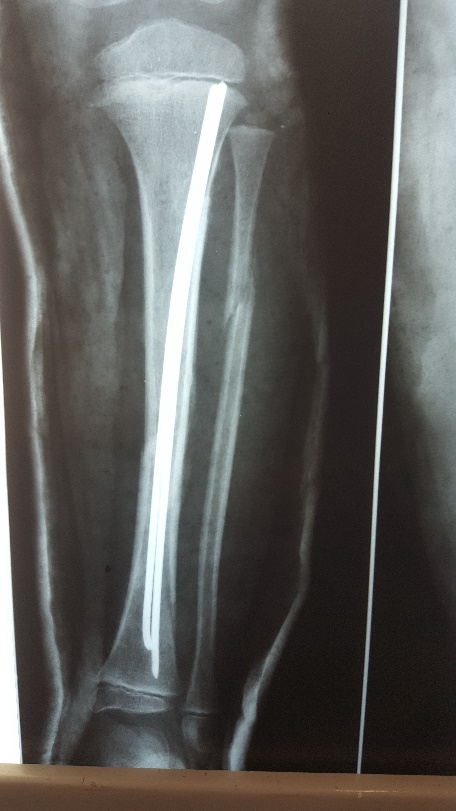

Այս ուսումնասիրությունը հիմնված է 21 հիվանդների (17 տղա, 4 աղջիկ) շարունակական խմբի բուժման արդյունքների վերլուծության վրա, որոնք ենթարկվել են տիտանե էլաստիկ մեխերով վիրահատության։ Հիվանդների տարիքը եղել է 4 տարեկանից մինչև 16 տարեկան։ 9 երեխայի մոտ կոտրվածքի պատճառ է հանդիսացել ձեռքի վրա անկումը, մնացածի մոտ կոտրվածքն առաջացել է վերջույթի ոլորման արդյունքում, վնասվածքի մեխանիզմը եղել է ուղիղ: 19 դեպքերում կոտրվածքները եղել են փակ, իսկ 2 դեպքում՝ բաց։ Ըստ վնասվածքի տեղայնացման՝ դրանք եղել են դիաֆիզար կոտրվածքներ (15 դեպք), պրոքսիմալ մետաֆիզի մակարդակի կոտրվածք (3 դեպք) և հեռավոր մետաֆիզի՝ (3 դեպք): Կոտրվածքային գծի բնույթի համաձայն՝ դիաֆիզային կոտրվածքներից հայտնաբերվել են 6 լայնակի, 4 թեք, 5 պտուտակաձև։ Մի տղայի մոտ (4 տարեկան), որի մոտ առկա էր սրունքի մ/3-ի բաց թեք կոտրվածք տեղաշարժով և մաշկի մինուս հյուսվածքներով, կատարվել է նաև վերքերի առաջնային վիրաբուժական մշակում և կարում՝ ռետինյա արտաթորիչներով։ Սակայն մի քանի շաբաթ անց սկսվել է մաշկի նեկրոզ։ Այդ իսկ կապակցությամբ կատարվել է երկրորդ վիրահատական միջամտությունը։ Կատարվել է մաշկի աուտոտրանսպլանտացիա։ Մաշկի կտորները վերցվել են առողջ ազդրի առաջային մակերեսից: (Նկ 1)

Օգտագործված մեթոդները համահունչ էին հեղինակների նկարագրած վիրաբուժական տեխնիկայի հետ: Հիմնական սկզբունքներն էին՝ ձողերի տրամագիծը, որը համապատասխանում է մեդուլյար լուսանցքի տրամագծի 30-40% -ին, ձողերի թեքությունները նույնական են, բայց հակառակ ուղղորդված և տեղակայված են կոտրվածքի մակարդակում, հարմարեցված վիրաբուժական գործիքների օգտագործումը: